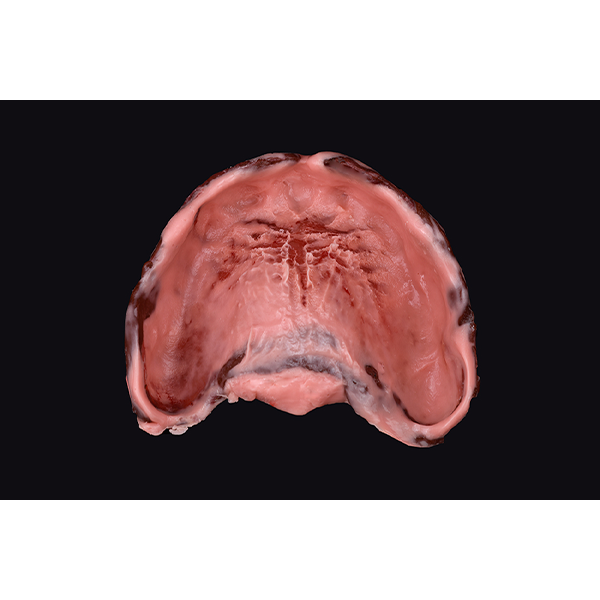

Après la mise en moufle et l'ébouillantage, les dents ont été repositionnées, conditionnées et des caractérisations blanchâtres, pourpres, orange clair, bleues et roses ont d'abord été réalisées au niveau du le bouclier labial. La base a ensuite été incrustée de résines pour prothèses de couleurs orange-rouge, rouge foncé, rouge clair, rose et rose foncé, et tous les polymères à chaud ont été pressés en une seule fois. Après le stockage sous pression, les prothèses finies ont été démouflées, finies et polies. La stratification anatomique tridimensionnelle de VITAPAN EXCELL en masse d'émail, de collet et de dentine avait un aspect absolument naturel dans l'anatomie muco-gingivale reproduite de la base prothétique. Le patient a pu s'habituer rapidement à sa nouvelle prothèse, notamment grâce à l'effet esthétique réussi. Après une courte phase d'adaptation et des corrections minimes dans l'environnement biodynamique, il s'est très bien débrouillé avec sa première restauration prothétique amovible complète et en était pleinement satisfait.